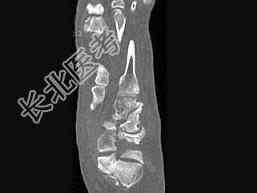

- 单项选择题男,56岁, 踝关节肿胀,有糖尿病史, 结合图像,最可能的诊断是 ( )

A、创伤性关节炎

B、退行性关节病

C、痛风

D、类风湿关节炎

E、神经性关节病